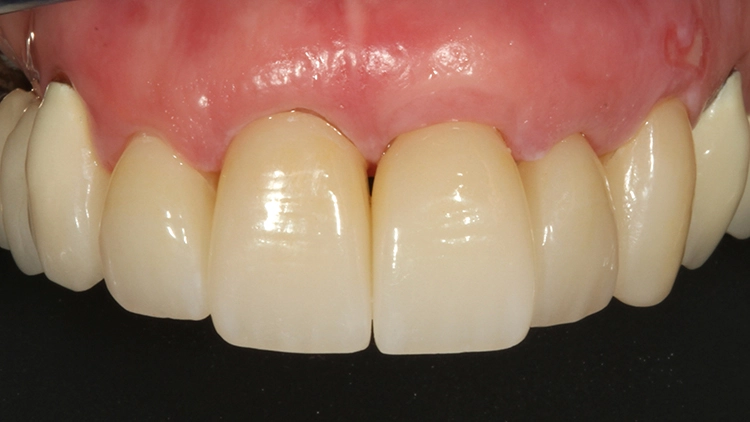

Bis zur definitiven prothetischen Versorgung sollte aufgrund etwaiger Gewebeveränderungen 6 Monate gewartet werden. Nach dieser Wartezeit zeigte sich ein stabiles, rezidivfreies parodontalchirurgisches Behandlungsergebnis (Abb. 8 und 9).

Bei der jetzt anstehenden Teilkronen- bzw. Veneerversorgung der Zähne 12 bis 23 blieb zunächst die Frage des keramischen Restaurationsmaterials zu klären. Neben der bewährten und hochästhetischen glasbasierten Keramik [2,8,10,14–16] eignen sich heutzutage transluzente Zirkonoxidmaterialien hervorragend für die ästhetische Ausgestaltung von Frontzahnbereichen [11], da sie genauso gut verklebt werden können wie Glaskeramiken [9,23].

Gerade im Bereich parafunktional gefährdeter Areale punktet das gegenüber der klassischen Glaskeramik doch deutlich bruchfestere Vollzirkonmaterial. Da bei der Patientin bereits mehrfach Füllungen und Inzisalkanten frakturierten, fiel in diesem Fall die Materialauswahl auf ein hochtransluzentes, polychromes Vollzirkon (zolid fx multilayer, Amann Girrbach), welches mit Ceramotion ZR (Dentaurum) verblendet wurde. Hergestellt wurde die Arbeit (Abb. 10 und 11) im eigenen Meisterlabor durch ZTM Richard Bohrer.